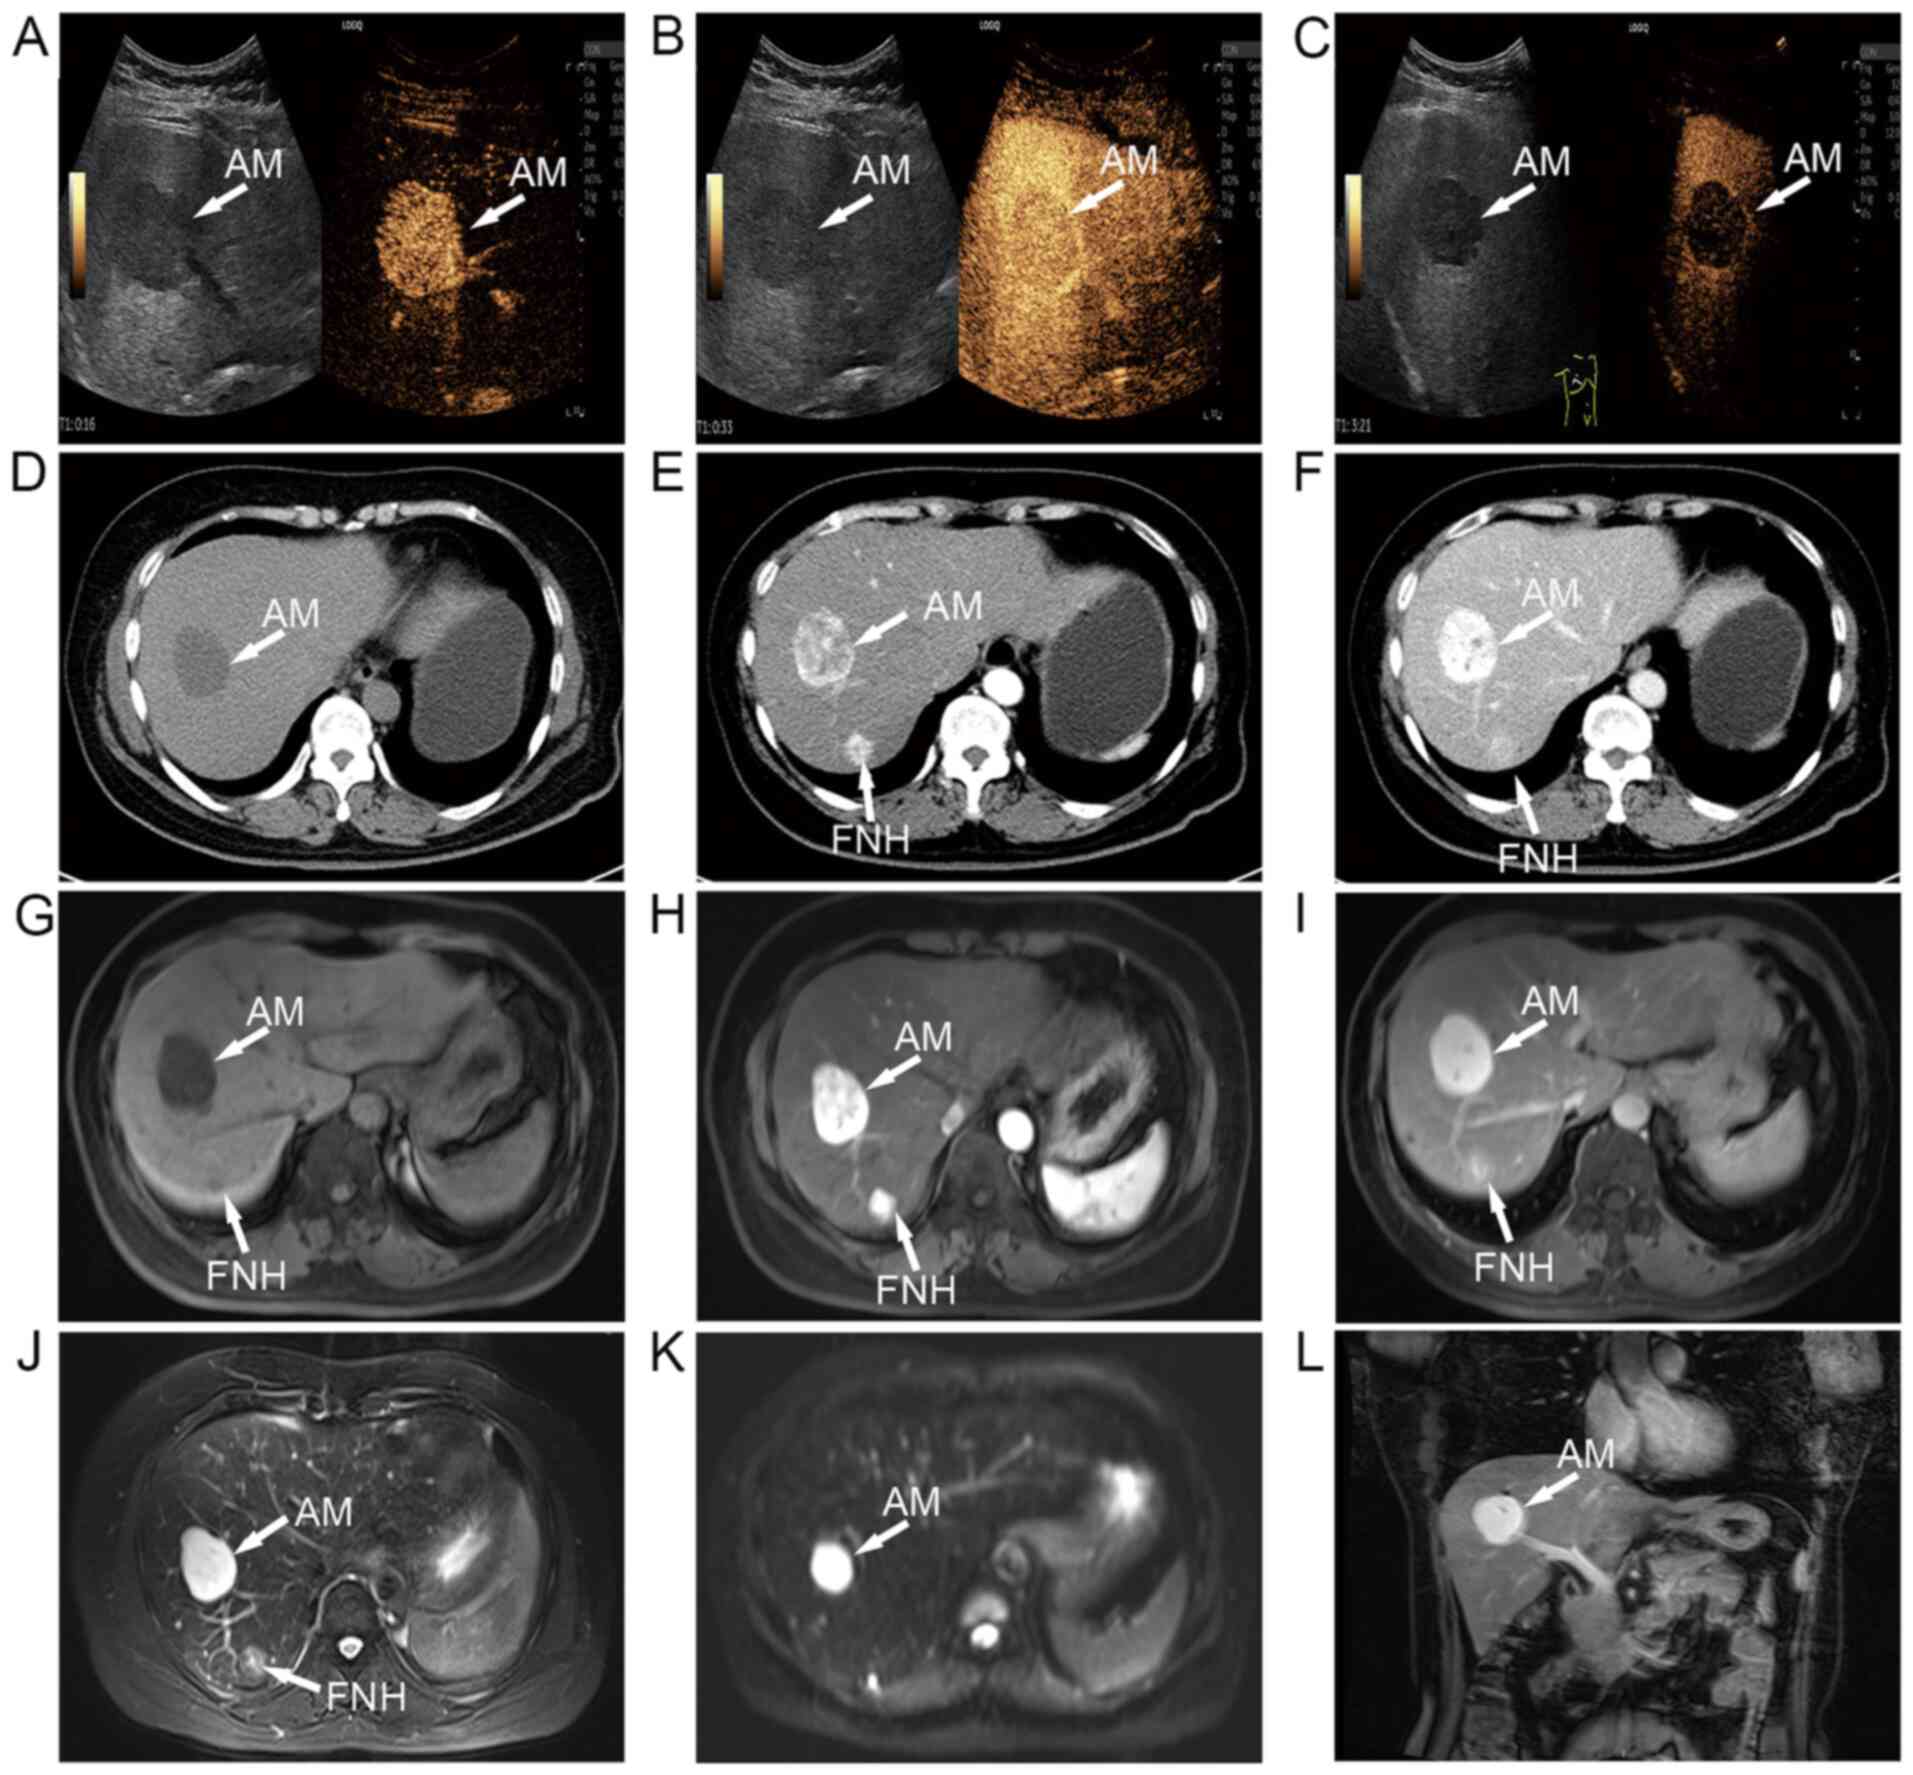

Angiomyxoma coexisting with focal nodular hyperplasia: A case report

Angiomyxoma (AM) occurs almost exclusively in the soft tissues of the pelvic and perineal regions. AM is a highly uncommon condition that can be easily misdiagnosed when it is present in other regions of the body. The current study presents a case in which AM of the liver coexisted with focal nodular hyperplasia (FNH). A 56‑year‑old woman presented with two space‑occupying lesions of the liver without any other clinical symptoms, and it was not easy to definitively diagnose the two intrahepatic lesions by imaging examinations. Due to the low incidence of AM in the liver, precise and clear clinical information on the condition is still unavailable, and the lesion was initially misdiagnosed as other hepatic tumors preoperatively. Once a tumor resection had been performed, a histopathological examination revealed that the microscopic features of the lesions were consistent with those of AM and FNH. The patient was followed up for 1 year, and no recurrence or metastasis was found. Surgical excision is an effective treatment for AM, and long‑term follow‑up is essential due to the risk of recurrence. The joint presentation of AM and FNH is rare in clinical practice, and although FNH of the liver is commonly reported, the difficulty of diagnosis increases when both conditions occur at the same time. Therefore, it is necessary to assist clinicians in making informed decisions regarding diagnosis and treatment.